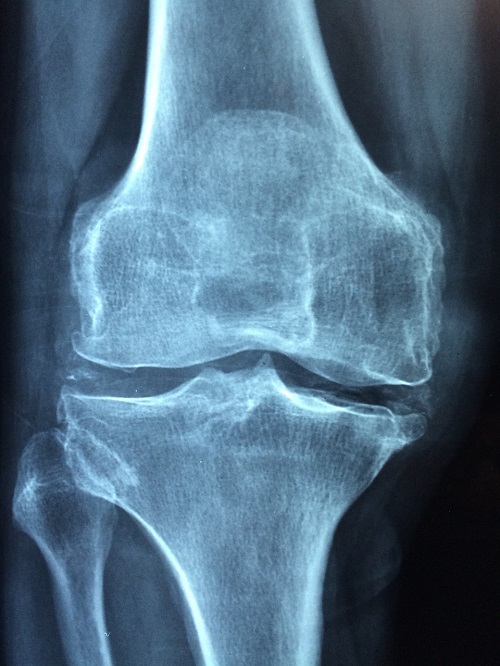

X-ray (엑스레이)

X-ray는 뼈와 관절의 상태를 확인할 수 있는 가장 일반적인 영상 검사 방법입니다. 연골 자체는 X-ray에서 보이지 않지만, 연골이 손상되어 관절 간격이 좁아진 경우 이를 통해 감지할 수 있습니다. 또한 관절 주변의 뼈에 생긴 돌기(골극)도 확인할 수 있습니다.